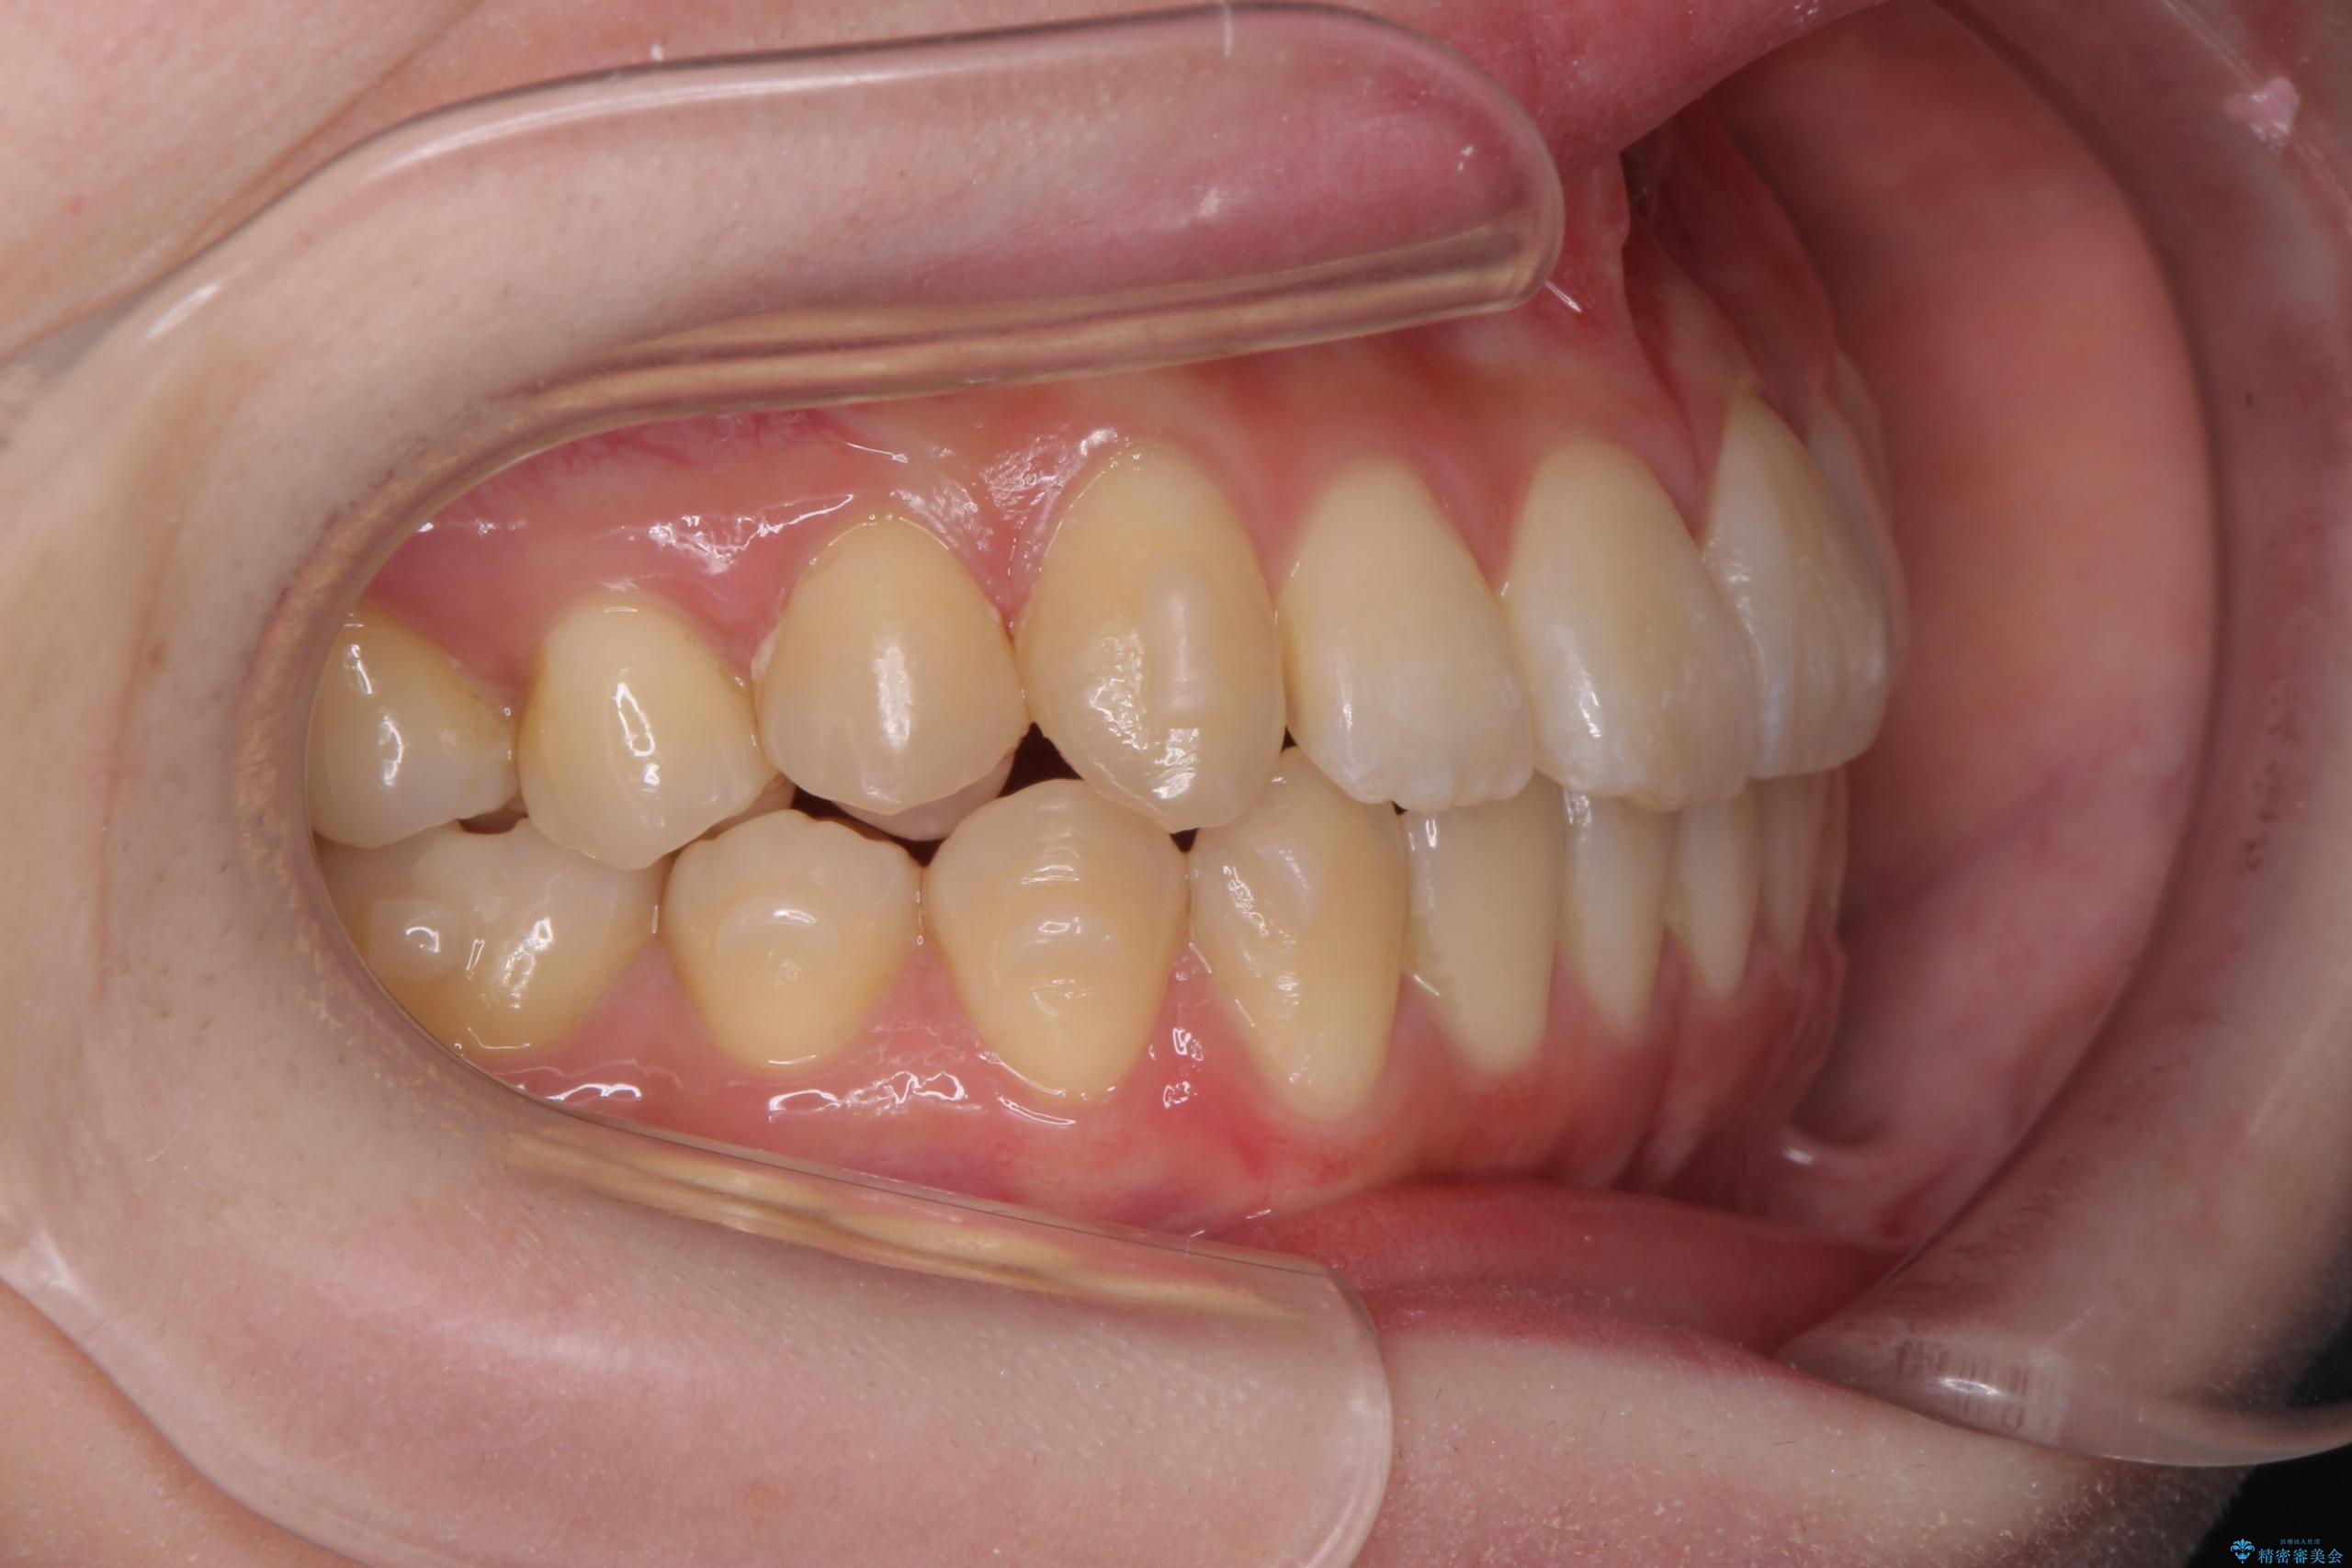

前歯のねじれが気になる、歯並びを改善したいとご来院された患者様です。

歯のねじれをきれいに取るのは、インビザライン(マウスピース矯正)だけでは難しい動きです。そのため、事前に4か月間の部分ワイヤー矯正を行い、治療期間を短くし、より美しい仕上がりを目指す計画です。

前歯が綺麗に並び、大変ご満足いただけました。